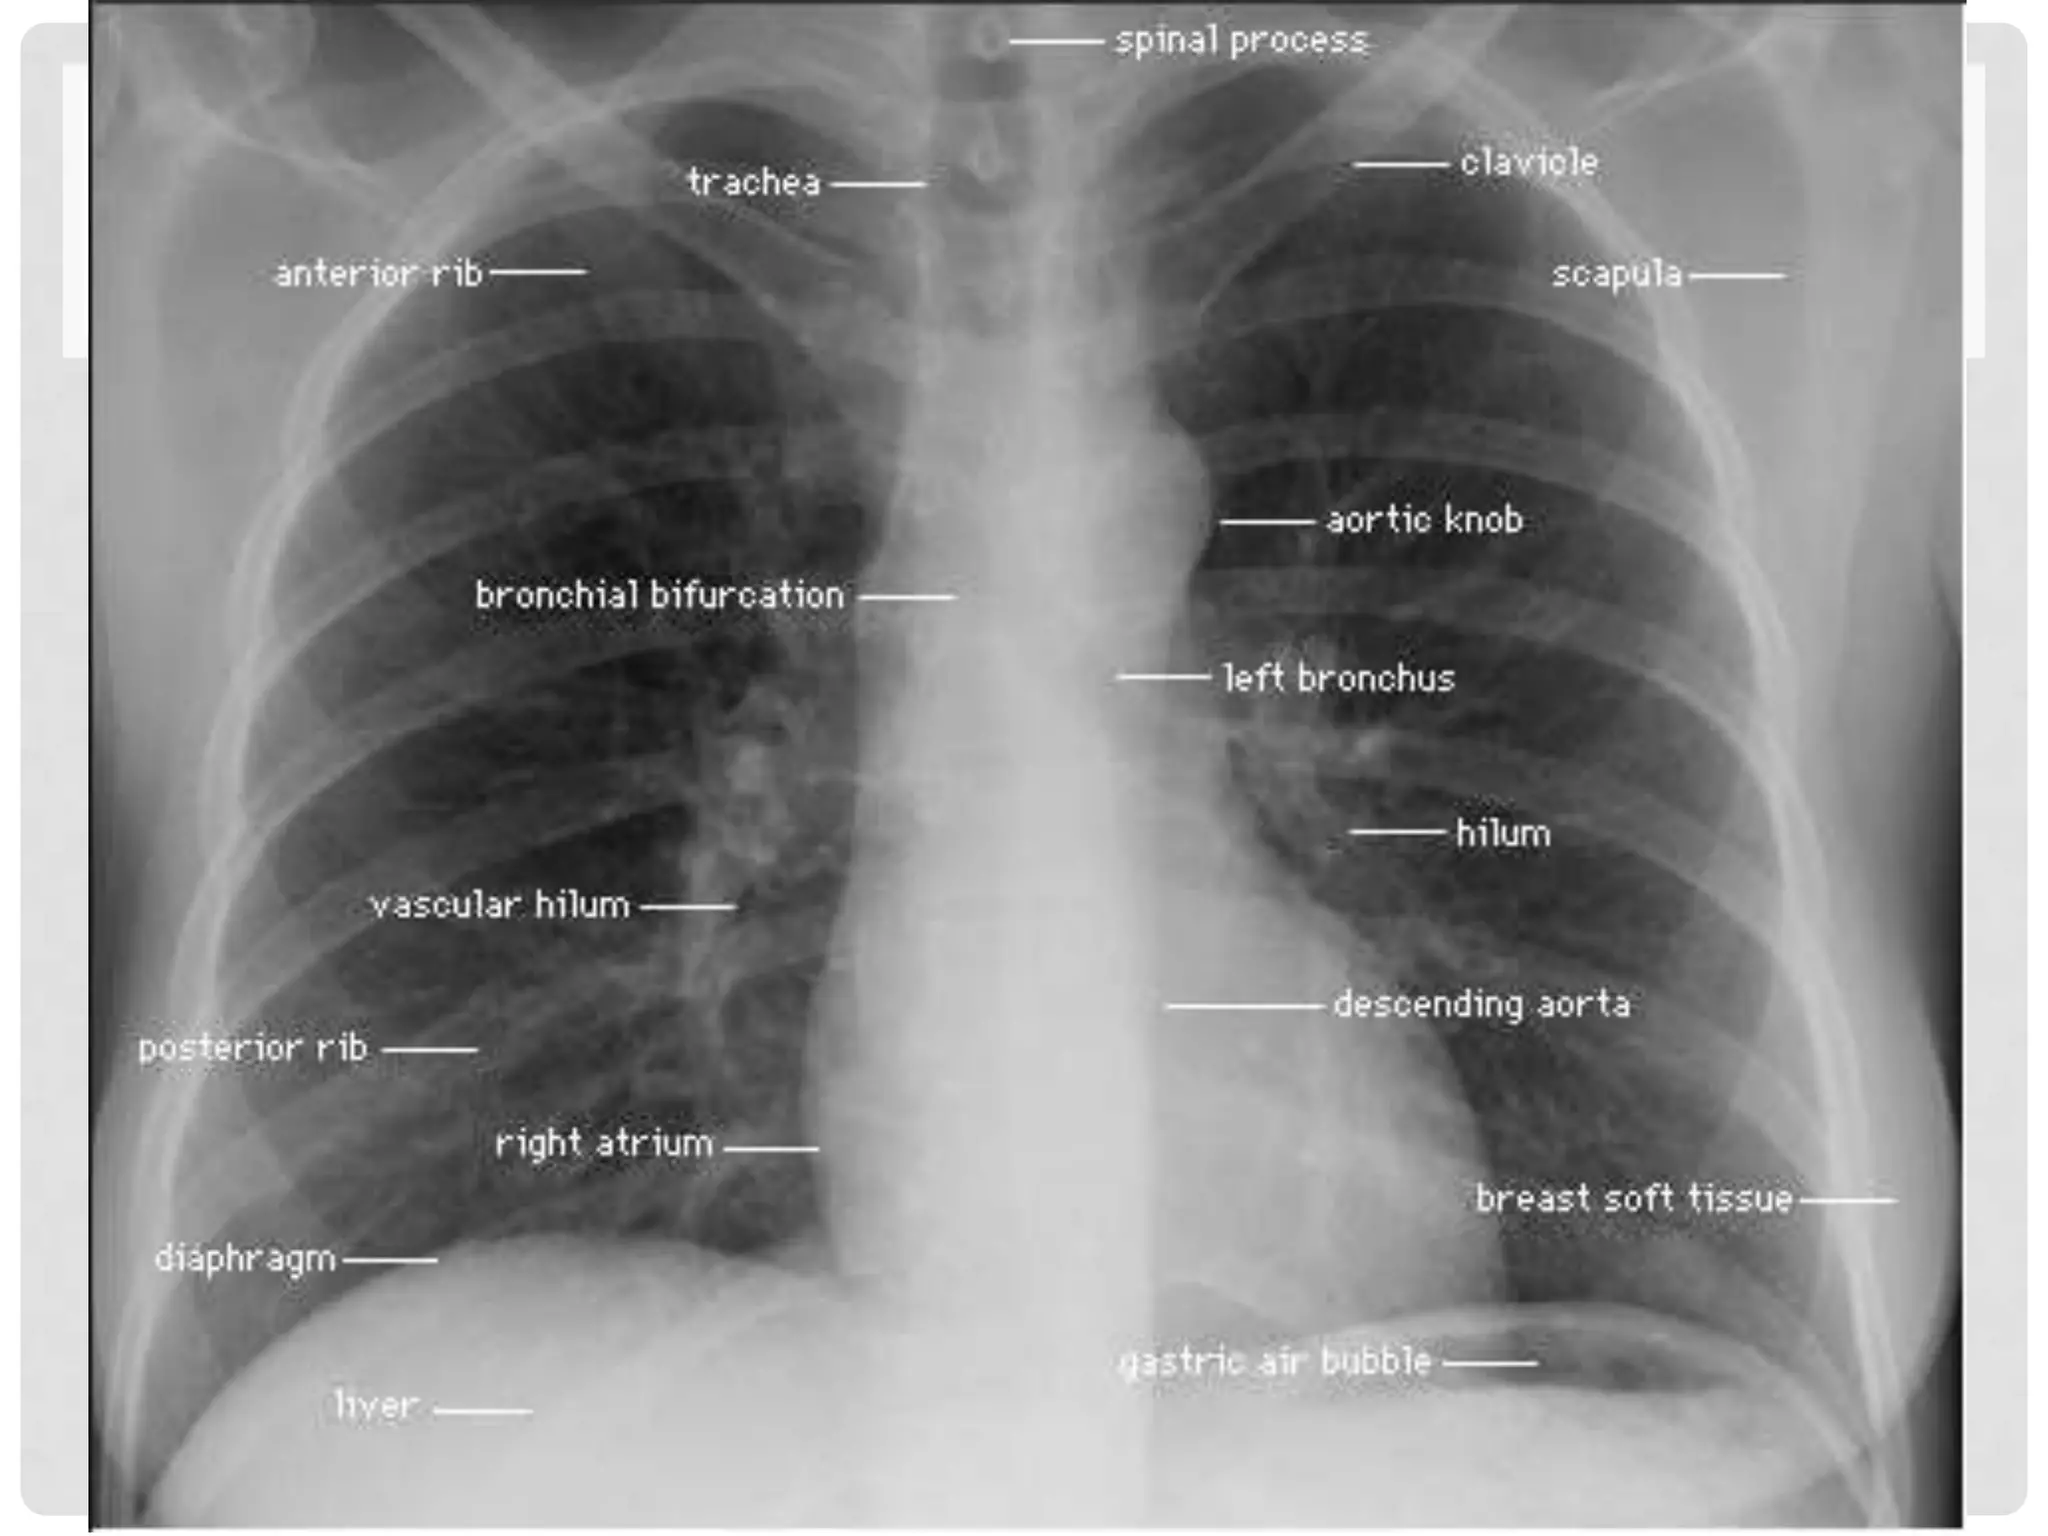

Normal Chest X-ray

CHEST X-RAY

STRUCTURES TO BE IDENTIFIED

•   1 SVC

•   2 IVC

•   3 RA

•   4 RV

•   5 LV